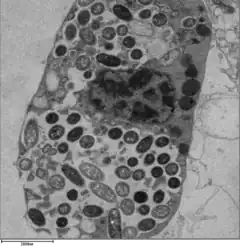

In nature, L. pneumophila infects freshwater and soil amoebae of the genera Acanthamoeba. The mechanism of infection is similar in amoeba and human cells.[4][5]

For Legionella to survive within macrophages and protozoa, it must create a specialized compartment known as the Legionella-containing vacuole (LCV). Through the action of the Dot/Icm secretion system, the bacteria are able to prevent degradation by the normal endosomal trafficking pathway and instead replicate. Shortly after internalization, the bacteria specifically recruit endoplasmic reticulum-derived vesicles and mitochondria to the LCV while preventing the recruitment of endosomal markers such as Rab5a and Rab7a. Formation and maintenance of the vacuoles are crucial for pathogenesis; bacteria lacking the Dot/Icm secretion system are not pathogenic and cannot replicate within cells, while deletion of the Dot/Icm effector SdhA results in destabilization of the vacuolar membrane and no bacterial replication.[24][25]